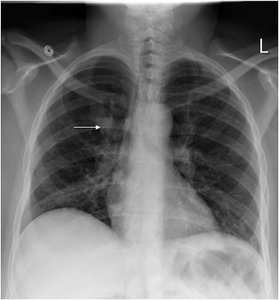

Lobe of Azygos Vein and Accessory Lung

Lobe of Azygos Vein: An anatomical variant appearing in the right lung, visible on chest X-ray.